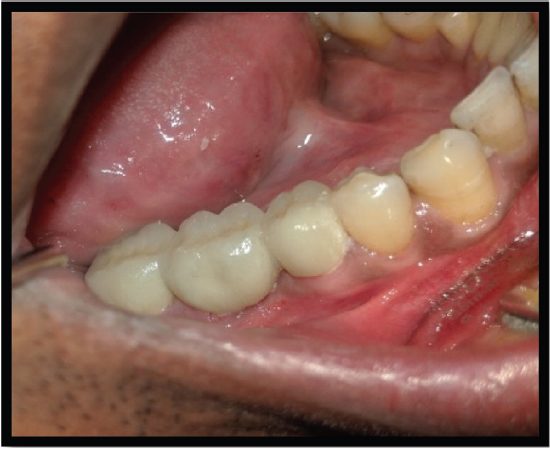

A 26-year-old female patient presented to the Faculty of Dental Sciences at King George’s Medical University, Lucknow, with the primary complaint of pain and sensitivity in the right lower posterior region persisting for the past 3 months. The pain was triggered by mastication and was relieved thereafter. A radiograph (IOPA) revealed periodontal bone loss affecting the coronal third of the distal root compared to the mesial root, and it showed periapical radiolucency at the distal root [Figure 7]. The periodontal support of the mesial root of tooth 46 was deemed adequate. Based on these findings, the diagnosis of chronic irreversible pulpitis associated with the lower right mandibular molar, along with furcation involvement, was established [Figure 8]. It was determined that the distal root should undergo hemisection subsequent to the completion of endodontic therapy for the tooth, in accordance with the methodology employed in Case 1 [Figures 9]. The hemisection of the distal root was executed using a vertical cut technique to effectuate separation. The crown was sectioned using a tapered fissure carbide bur until it reached the furcation. The procedure was thoroughly elucidated to the patient, and informed consent was duly obtained. Following the administration of local anesthesia, a mucoperiosteal flap was reflected to expose the area designated for hemisection. The hemisection procedure was performed on tooth 46 [Figure 10], after which the flapwas repositioned and sutured using 3-0 silk nonresorbable interrupted sutures. Definitive restorative therapy was conducted 6 weeks after the hemisection, which involved the placement of a three-unit porcelain fused-to-metal fixed partial denture to replace the distal root of the mandibular first molar, second premolar, and second molar [Figure 11]. At the 1-year follow-up appointment, the patient reported being asymptomatic.

Figure 7. IOPAR showing grossly carious tooth

Figure 8. IOPAR showing involved furcation